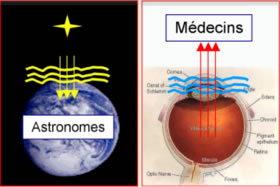

Les techniques développées par les astronomes pour

vaincre les effets de la turbulence atmosphérique peuvent

s'appliquer à l'examen in vivo du tissu rétinien.